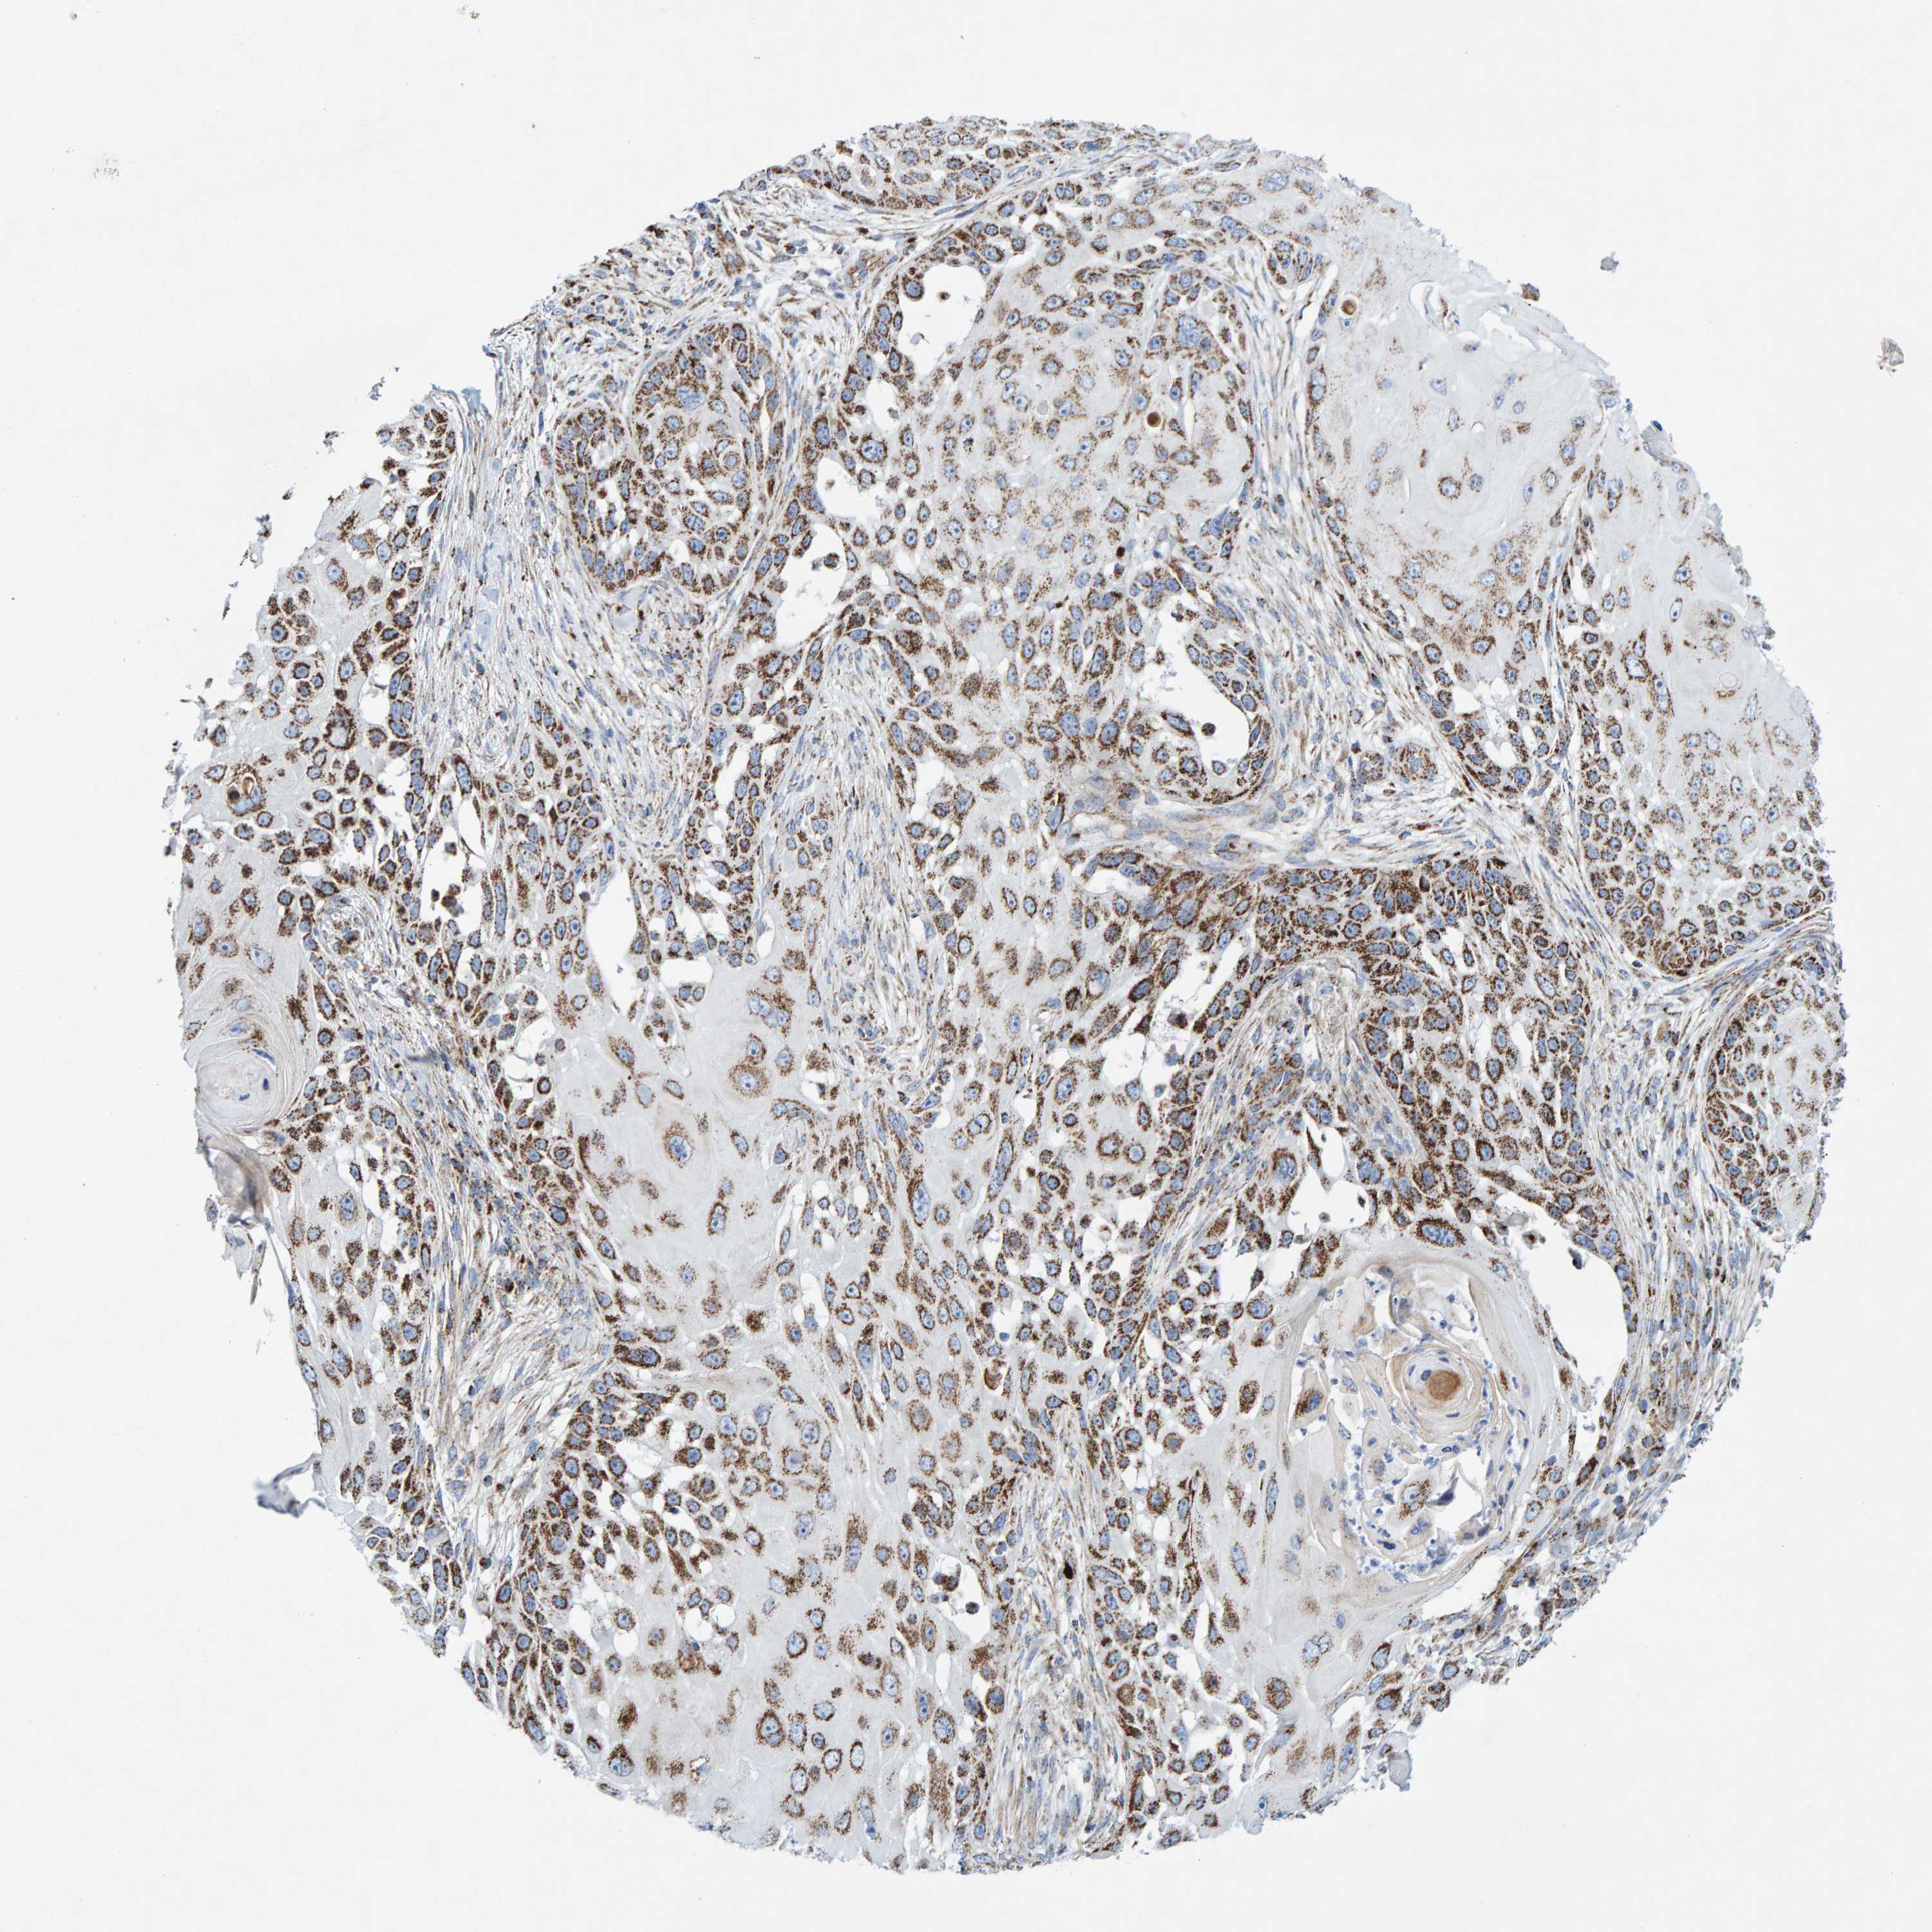

SKIN CANCER - Protein expressioni

A mouse-over function shows sample information and annotation data. Click on an image to view it in a full screen mode. Samples can be filtered based on level of antibody staining by selecting one or several of the following categories: high, medium, low and not detected. The assay and annotation is described here.

Antibody stainingi

Antibody staining in the annotated cell types in the current human tissue is reported as not detected, low, medium, or high, based on conventional immunohistochemistry profiling in selected tissues. This score is based on the combination of the staining intensity and fraction of stained cells.

Each image is clickable and will lead to virtual microscopy that enables deeper exploration of all samples and also displays staining intensity scores, fraction scores and subcellular localization as well as patient and tissue information for each sample.

Antibody HPA023262

Squamous cell carcinoma, NOS